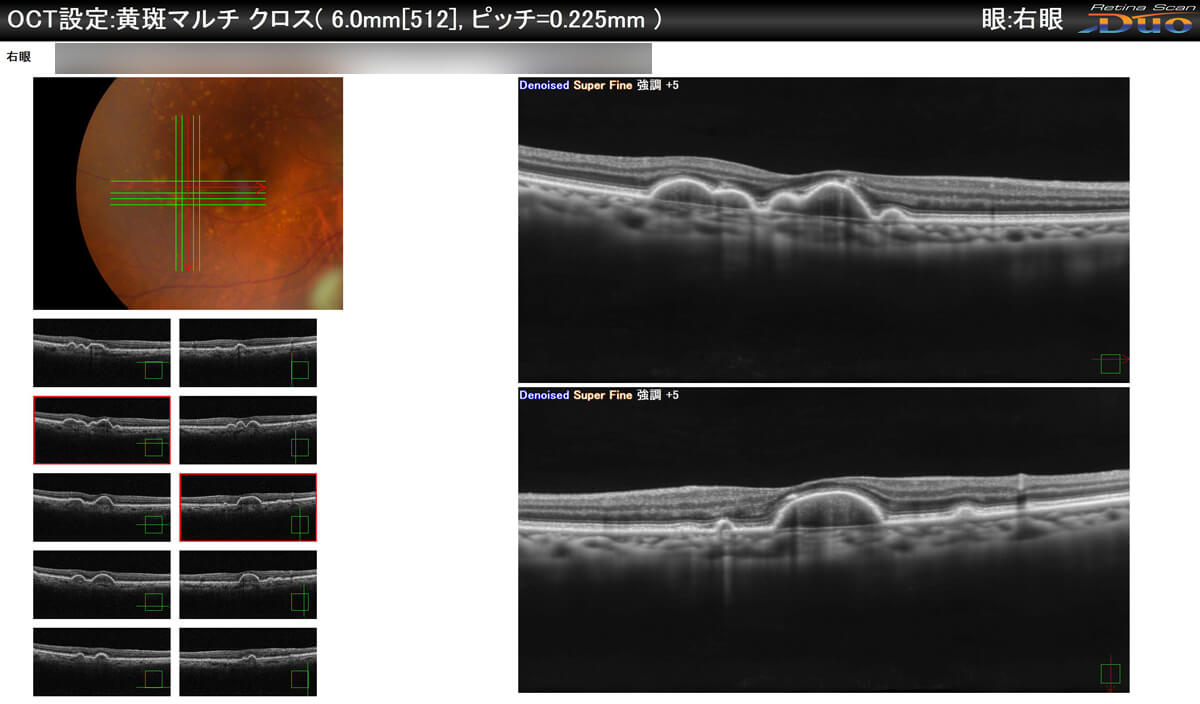

特長③ 後極部を断層撮影・3D解析できます

- 黄斑部疾患

- 黄斑部に疾患が生じた場合、物が歪んで見えるのが特徴です。見ようとする場所が見づらくなりますので、散瞳による眼底検査をお勧めします。

対象疾患:加齢黄斑変性症(黄斑部疾患)・網膜変性疾患 など

- OCT黄斑部撮影

クリックすると大きい写真がご覧になれます